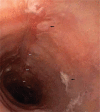

Results: Dysphagia to solid foods was the leading symptom, and endoscopic findings included white exudates, longitudinal furrows, and concentric mucosal rings, all suggestive for EoE. Diagnosis relied on histological findings in esophageal mucosal biopsies (>30 eosinophils per high power field).He was treated with topical steroids for 8 weeks, symptoms improved gradually and the patient remained in remission at the 8-month follow-up.